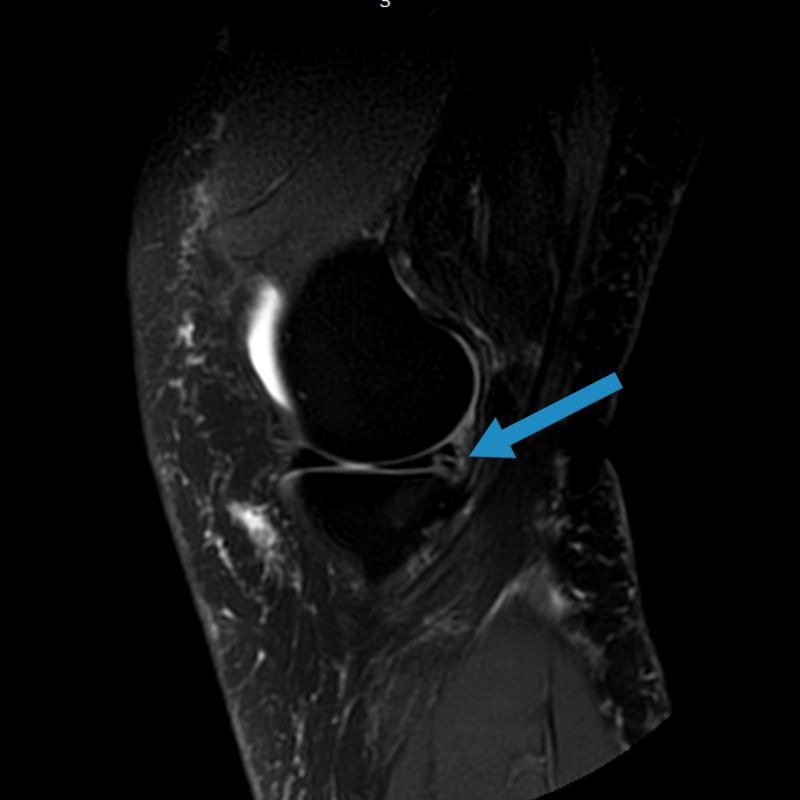

✅Повредила внутренний мениск во время падения. Говорят" нужна операция". А можно обойтись без операции? На МРТ повреждение заднего рога в